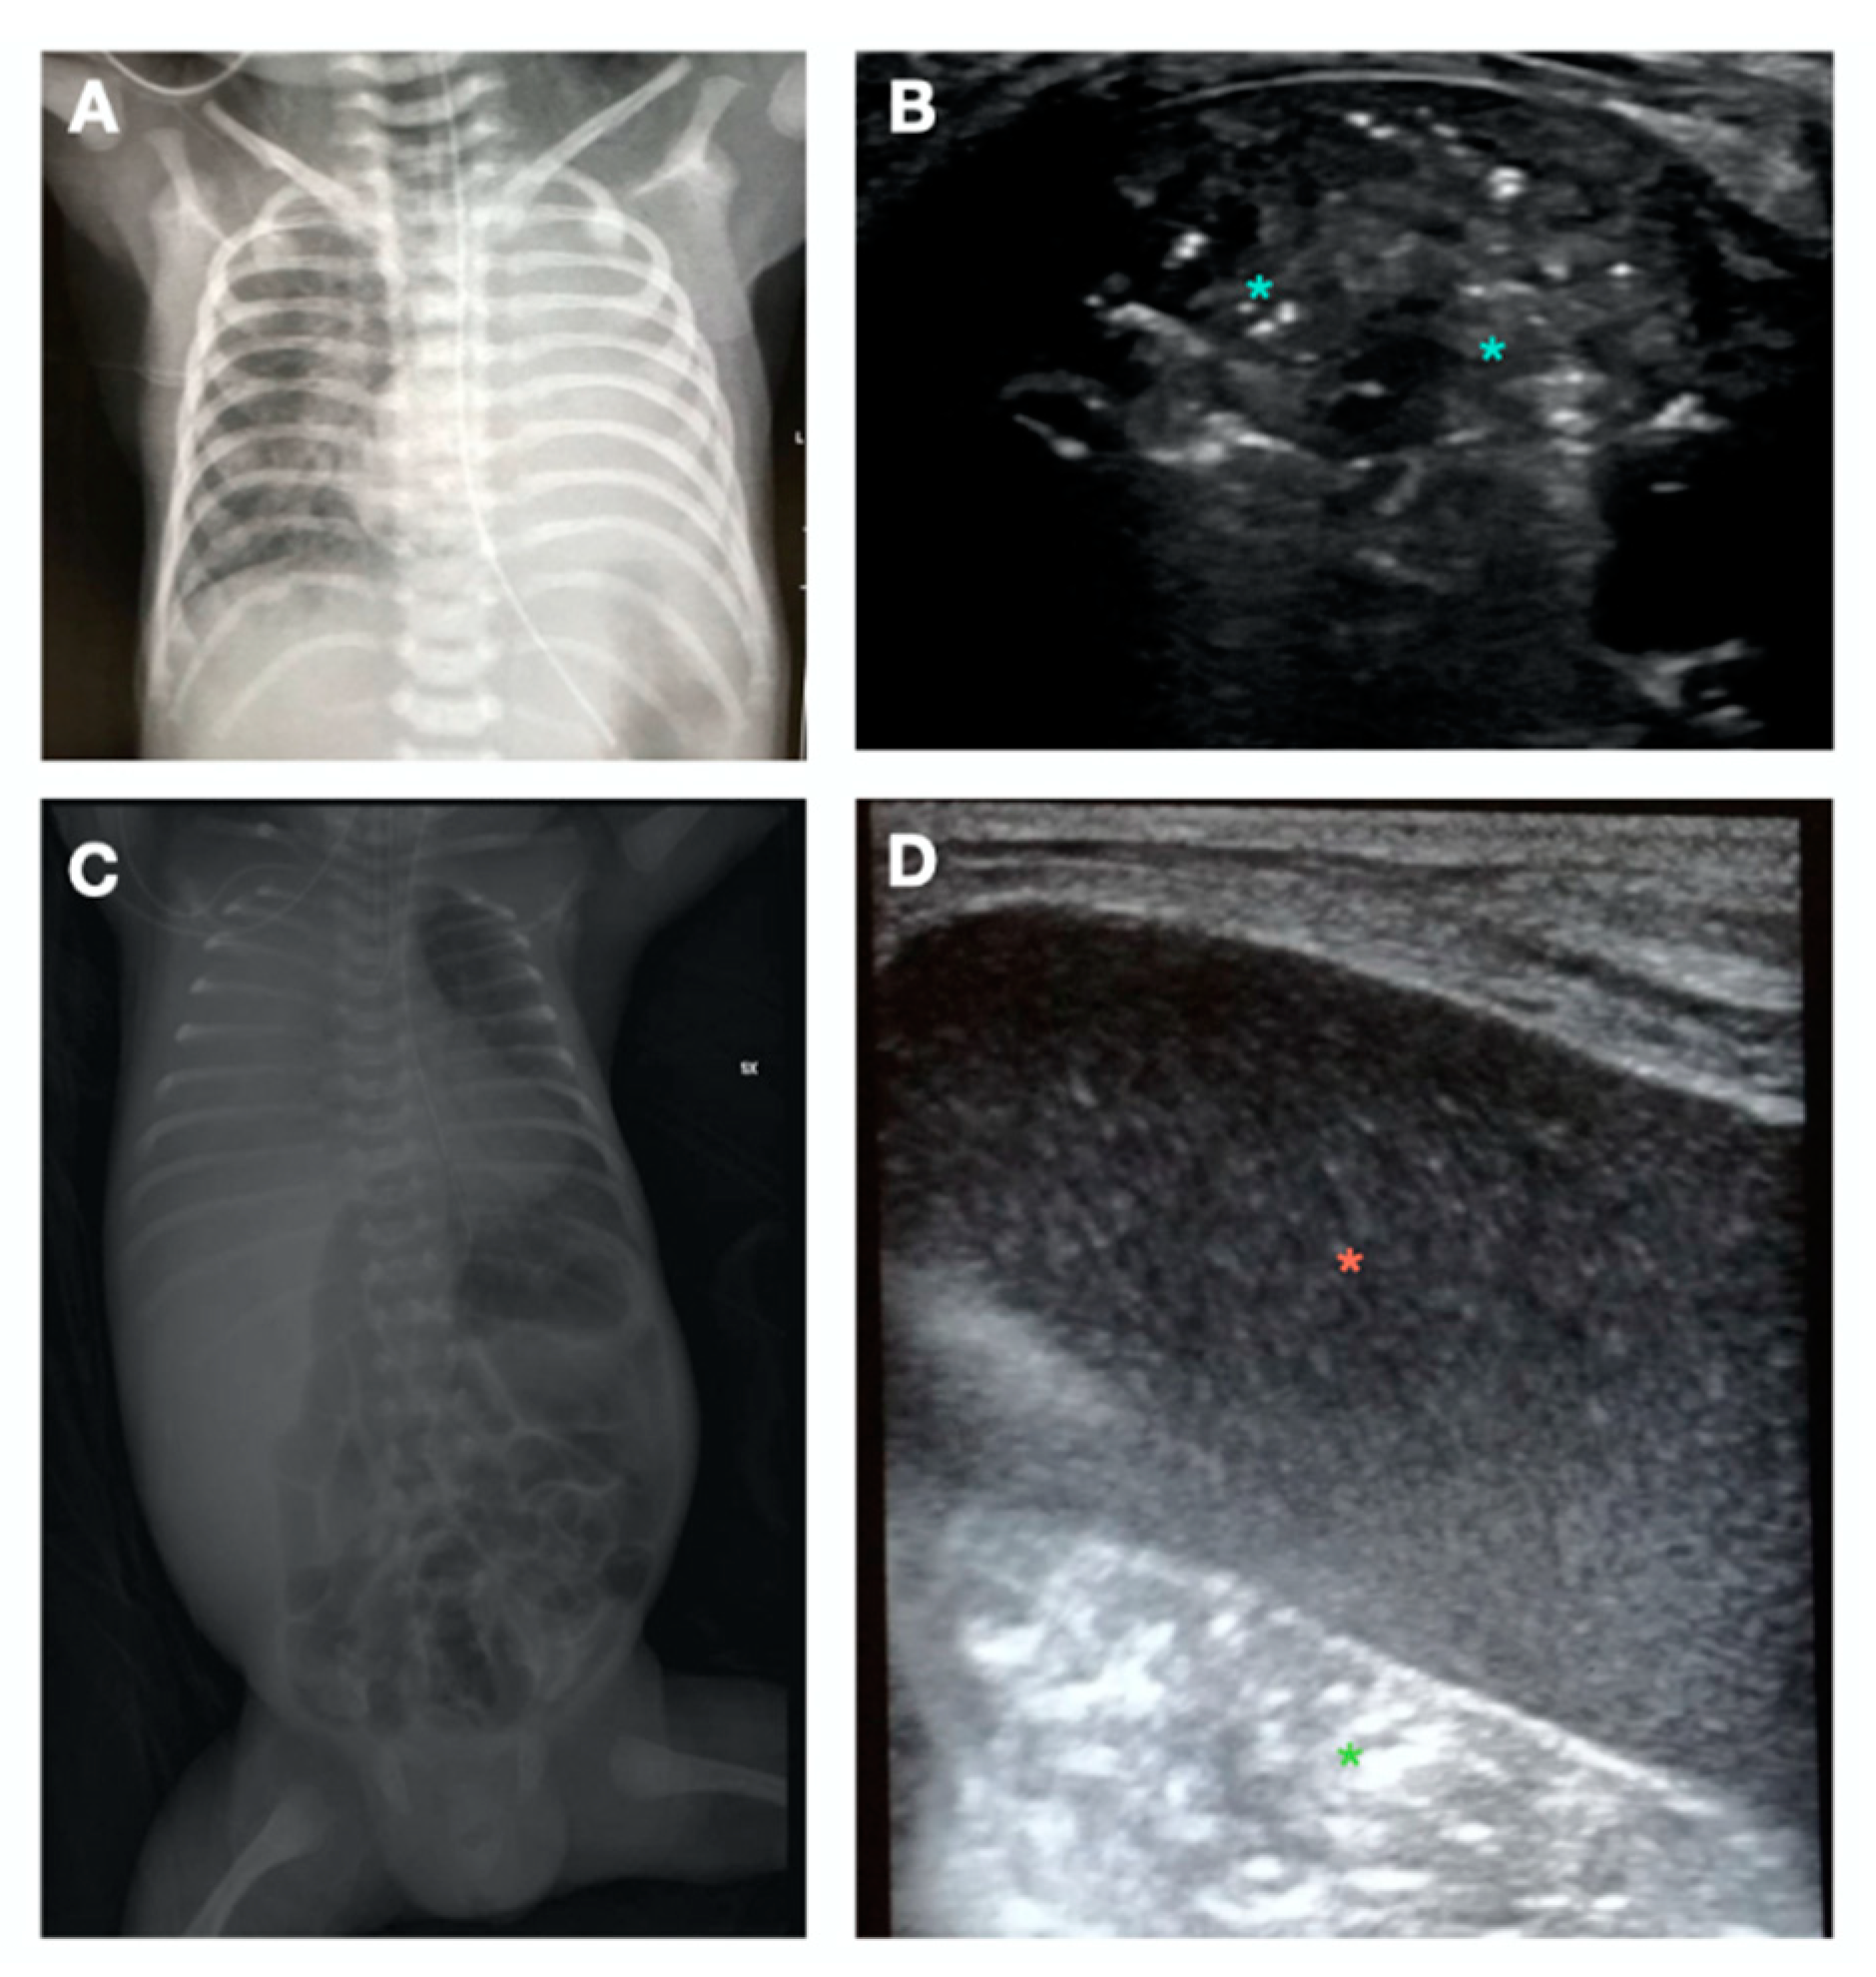

- A-Pattern (Figure 2A), normally aerated lung (aeration score = 0): A-lines, bilateral lung sliding (Video S2). The A-pattern in the absence of lung sliding suggests the presence of pneumothorax. In that case the lung point needs to be searched for. The lung point is point where the pneumothorax ends and the normal contact between the parietal and visceral pleura is restored. The corresponding ultrasound image is a scan where the a normal sliding is detected right aside a static pleura, representing the loss of contact between the parietal and visceral pleura. Therefore after the lung point, the pleural space is filled with air and the pleural sliding is absent (Video S3);

- B1-pattern (Figure 2B), moderate loss of lung aeration (aeration score = 1): three or more B-lines occupying less than 50% of the scanned area;

- B2-pattern (Figure 2C), severe loss of aeration (aeration score = 2): coalescent B-lines, occupying more than 50% of the scanned area;

- White lung (Figure 2D): compact B-lines that cause the acoustic shadow of the ribs to disappear within the entire scanning zone, anteriorly and posteriorly without spared areas;